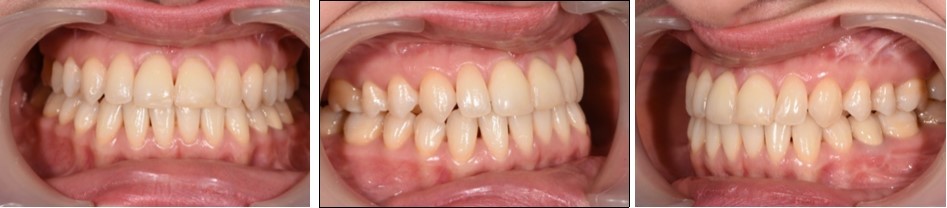

Post-surgical orthodontic treatment was started 4 weeks after the surgery. Wearing of bilateral box elastics was recommended in order to improve interdigitation. (Figure 6) The orthodontic treatment was finished on 0.019x0.025 SS archwires. Post-surgery cephalometric analysis revealed an increase in SNA value by 4 degrees (SNA 82 degrees) and a decrease in SNB value also by 4 degrees (SNB 79 degrees). The patient was now in a skeletal class I, with ANB 3 degrees. An examination of the soft tissue on the radiograph reveales a better relation between the upper and lower lip. (Figure 7).

Figure 6.Post-surgical intraoral photographs, with bilateral box elastics